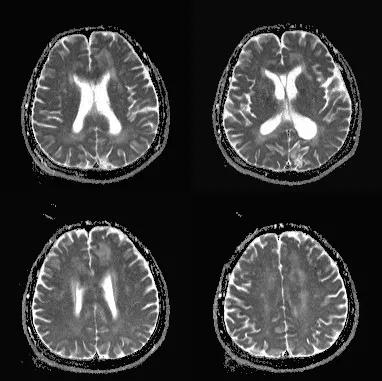

- 急性期表现为胼胝体弥漫性肿胀,T1WI呈稍低信号,T2WI及FLAIR呈稍高信号,以矢状位观察最佳,可单独累及胼胝体压部或整个胼胝体,DWI呈高信号,ADC图呈低信号,部分患者可观察到脑室周围白质或内囊受累,少见皮层受累,表现为扩散受限,不强化和强化病例均可见到。如果增强扫描可见胼胝体有不同程度强化,呈小灶状或不规则斑片状,系血脑屏障破坏所致(如本例),本例患者处于急性期。

原发性胼胝体变性急性期:T2WI矢状位(A)清晰观察到弥漫胼胝体病变,FLAIR呈高信号(B),DWI呈高信号(C),ADC图呈低信号。

31岁,男性,长期饮酒,出现急性失语、短期注意力和记忆力缺陷,胼胝体及半卵圆中心对称性异常信号,扩散受限,未见强化,经过维生素B1/6/9/12治疗后病灶吸收明显,诊断为原发性胼胝体变性急性期。

48岁,男性,长期饮酒过量20年,出现出现眩晕,胼胝体、侧脑室周围白质、内囊后肢对称性异常信号,扩散受限,诊断为原发性胼胝体变性急性期。